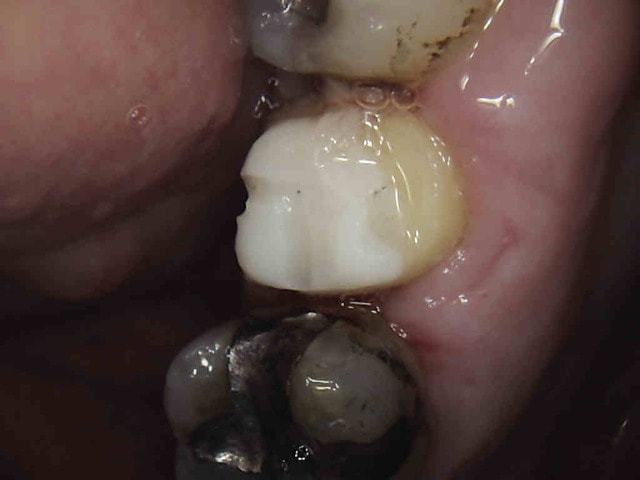

La semaine dernière légère douleur à la percussion sur 27. Et pourtant j'avais vu la radio après endo ! qui était nickel ( ou alors pas les yeux en face des trous ).

Admirez le chef d'oeuvre ! Pas évident de s'auto radiographier !

merde, alors sur la 7 il faut le faire exprès non ? C'est alésé en boulevard en plus !

Ca s'enlève bien les tenons zircone ? C'est plutôt rare d'en trouver. Ca m'arrive d'en poser mais je n'en ai enlevé aucun.

La classe oui. C'est du protilab, mais c'était une demande personnelle, juste pour tester !. Bizarrement, c'est pas la prothèse qui a merdé, ca remet les choses à leur place-)))))

bon premier essai, l'ic en ceram scellé au fuji fait de la résistance à l'arrache couronne. J'amène mon coronaflex kavo la prochaine fois et des fraises black and white komet. -)))

La couronne est virée. Reste l'inlay core en full zircone dur comme du béton.